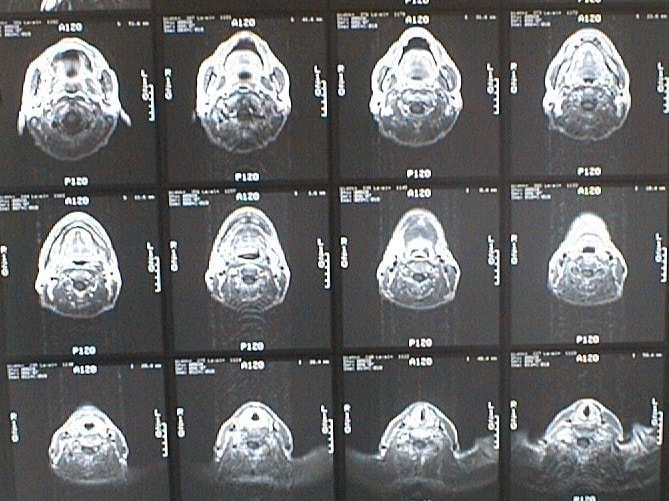

CT画像比較

入院当時CT画像②

入院3か月後癌消滅CT画像②